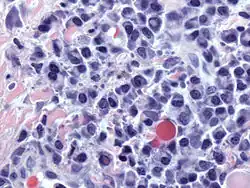

![]() Micrograph of malignant plasma cells (plasmacytoma), many displaying characteristic "clockface nuclei", also seen in normal plasma cells. H&E stain. | |

Plasma cells are large lymphocytes with abundant cytoplasm and a characteristic appearance on light microscopy. They have basophilic cytoplasm and an eccentric nucleus with heterochromatin in a characteristic cartwheel or clock face arrangement. Their cytoplasm also contains a pale zone that on electron microscopy contains an extensive Golgi apparatus and centrioles. Abundant rough endoplasmic reticulum combined with a well-developed Golgi apparatus makes plasma cells well-suited for secreting immunoglobulins.[4] Other organelles in a plasma cell include ribosomes, lysosomes, mitochondria, and the plasma membrane.